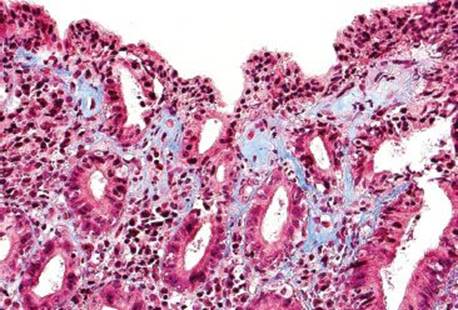

Figure 2.145 Collagenous gastritis pattern, olmesartan, (Masson’s trichrome). A trichrome stain of the previous case confirms that the pink band is composed of collagen. The surface epithelium has sheared away from the collagen in this deeper level, a finding highly characteristic of collagenous enteritis/colitis and not seen as often in the stomach. Note how the deep border of the collagen band is markedly irregular, appearing to seep between the glands as if the collagen were candle wax drippings.